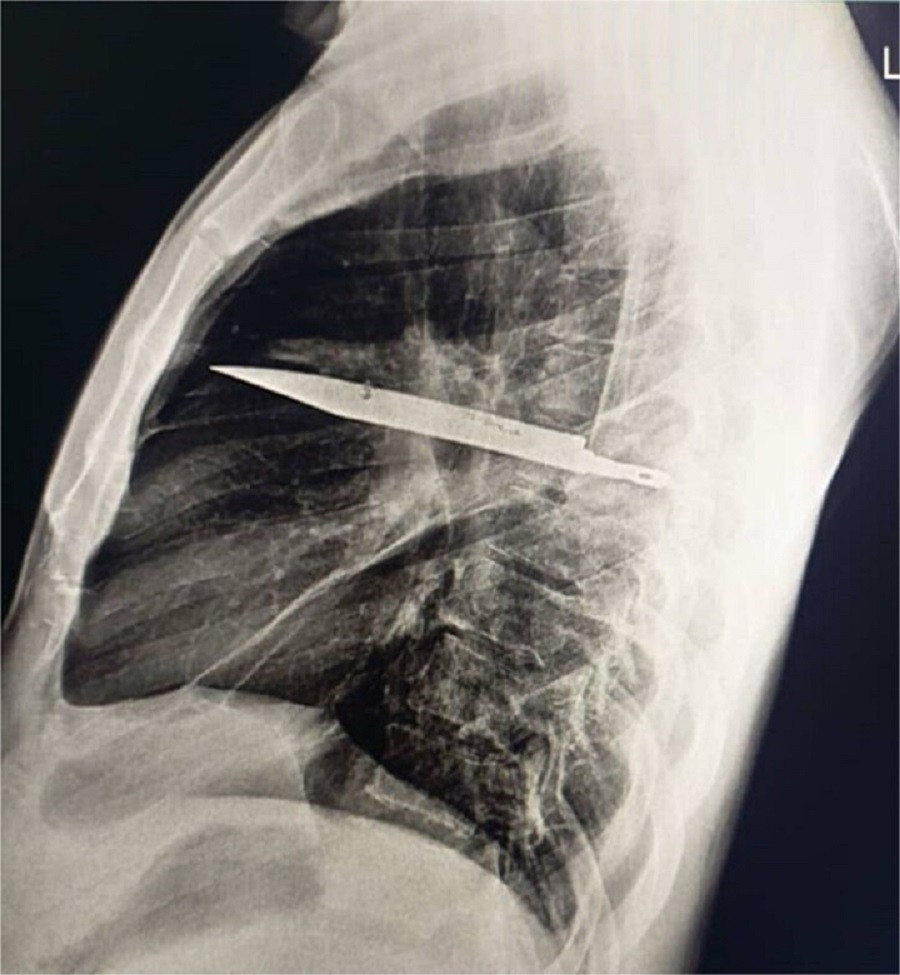

Στα οχτώ χρόνια που ακολούθησαν είχε μία «ομαλή πορεία» μέχρι να προκύψει το πρόβλημα που τον έκανε να πάει στον γιατρό. Η ακτινογραφία έδειξε «μεταλλικό αντικείμενο»- ένα μαχαίρι- στο στήθος του. Είχε εισέλθει από την ωμοπλάτη και το περιέβαλε πύον και νεκρωτικός ιστός.

Αμέσως οι γιατροί έκαναν χειρουργική επέμβαση και αφαίρεσαν το μαχαίρι. Έπειτα από δέκα ημέρες ο 44χρονος πήρε εξιτήριο. Οι ερευνητές σημείωσαν ότι «παρότι ανέρρωσε καλά μετά την επέμβαση, υπήρχε σημαντικός κίνδυνος» το γεγονός ότι το μαχαίρι είχε μείνει στο σώμα του να προκαλέσει τον θάνατό του.